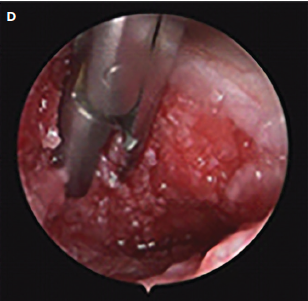

All special morphological and pathological features of the wounds were documented and photographed for the patient’s record (Figure 1C, 1D). Closure was defined as the formation of fibrous connection in the sinus tract or sinus cavity with disappearance of the original cavity and closure of the opening in the skin or mucosal surface.